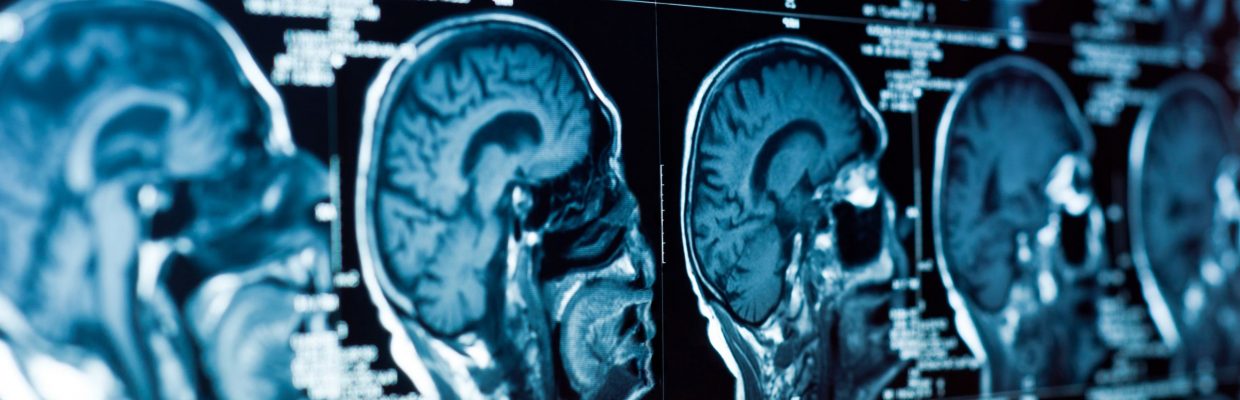

Our department has two MRI scanners – 3T and 1.5T – which enables our highly skilled staff to see more patients and undertake highly complex procedures.

- Magnetic Resonance Imaging (MRI)